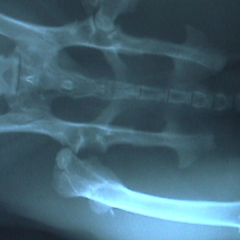

右の股関節が脱臼している。

時間がたっている場合は麻酔下で整復しても再脱臼する場合が多く、うまくいかないことが多い。

この状態では上に上がった大腿骨頭(丸い部分)が股関節側の骨に当たり痛みが出る。骨も正常な位置になく上に上がっている。 |